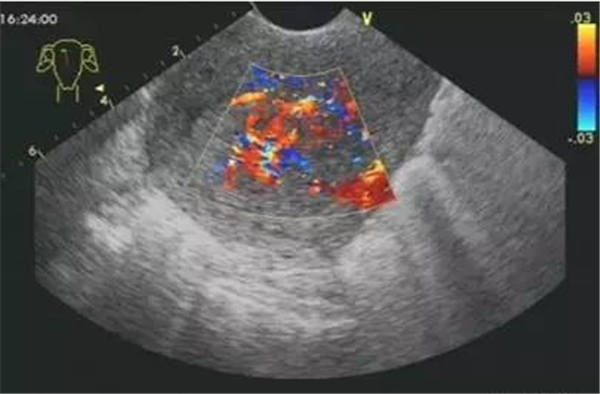

血栓

血栓是血栓性肺栓塞最典型的特征,位于右房或右室中的血栓可形态各异,而位于肺动脉内时则常表现为大块血栓,从主干延续至一侧或双侧肺动脉分支。右肺动脉主干血栓易于显示,左肺动脉因显示较短,血栓不易显示。此外,需注意将血栓与右心系统肿瘤相鉴别。

右心血栓 肺动脉血栓